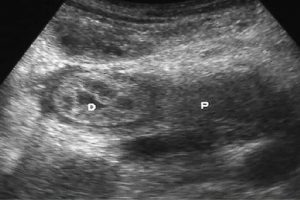

Diplomados en Ultrasonografía